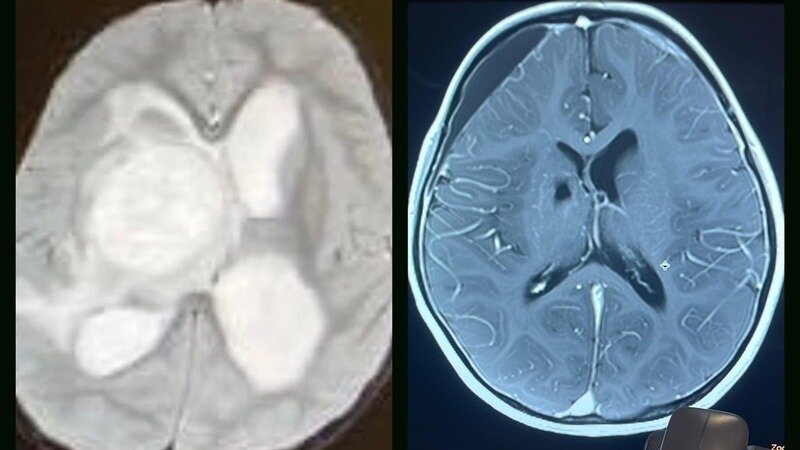

Picture TWO: Another pediatric cancer patient fighting ganglioglioma. Her mother refused chemo/radiation and this patient began full extract cannabis oil. The child's scan in 2021 on the left and two years later, almost cancer free.